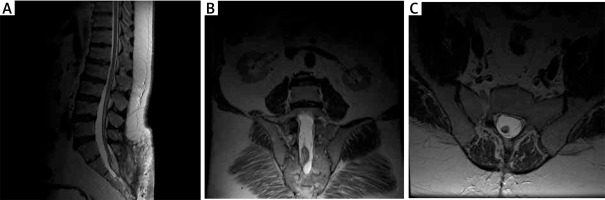

Ten months later, during another outpatient visit, MRI was performed (Figure 5). Clinically, the patient’s condition had improved since discharge from the neurosurgery department, pain was significantly reduced, and sphincter function did not deteriorate.

Figure 5

MRI scan at 12 months after surgery in 2 patients. A – MR T2 examination, postoperatively; visible postoperative wound, partially removed lipoma. B – MR T2 examination, postoperative coronal sections; remaining part of the adipoma is visible. C – MR T2 examination, postoperative axial sections